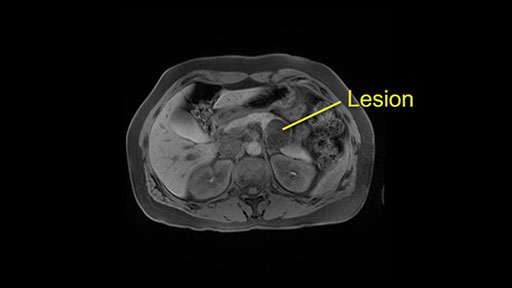

This is a 48-year old woman with history of kidney stones who was referred with an incidental finding of a lesion in the body of the pancreas. The multiseptated cystic lesion measures 3.2 x 3.9 x 4.3cm with an area of gadolinium-enhanced septal thickness. She was asymptomatic with no history of pancreatitis. There is no biliary dilatation and the spleen appeared normal. The plan is to do a laparoscopic distal pancreatectomy with possible splenectomy.